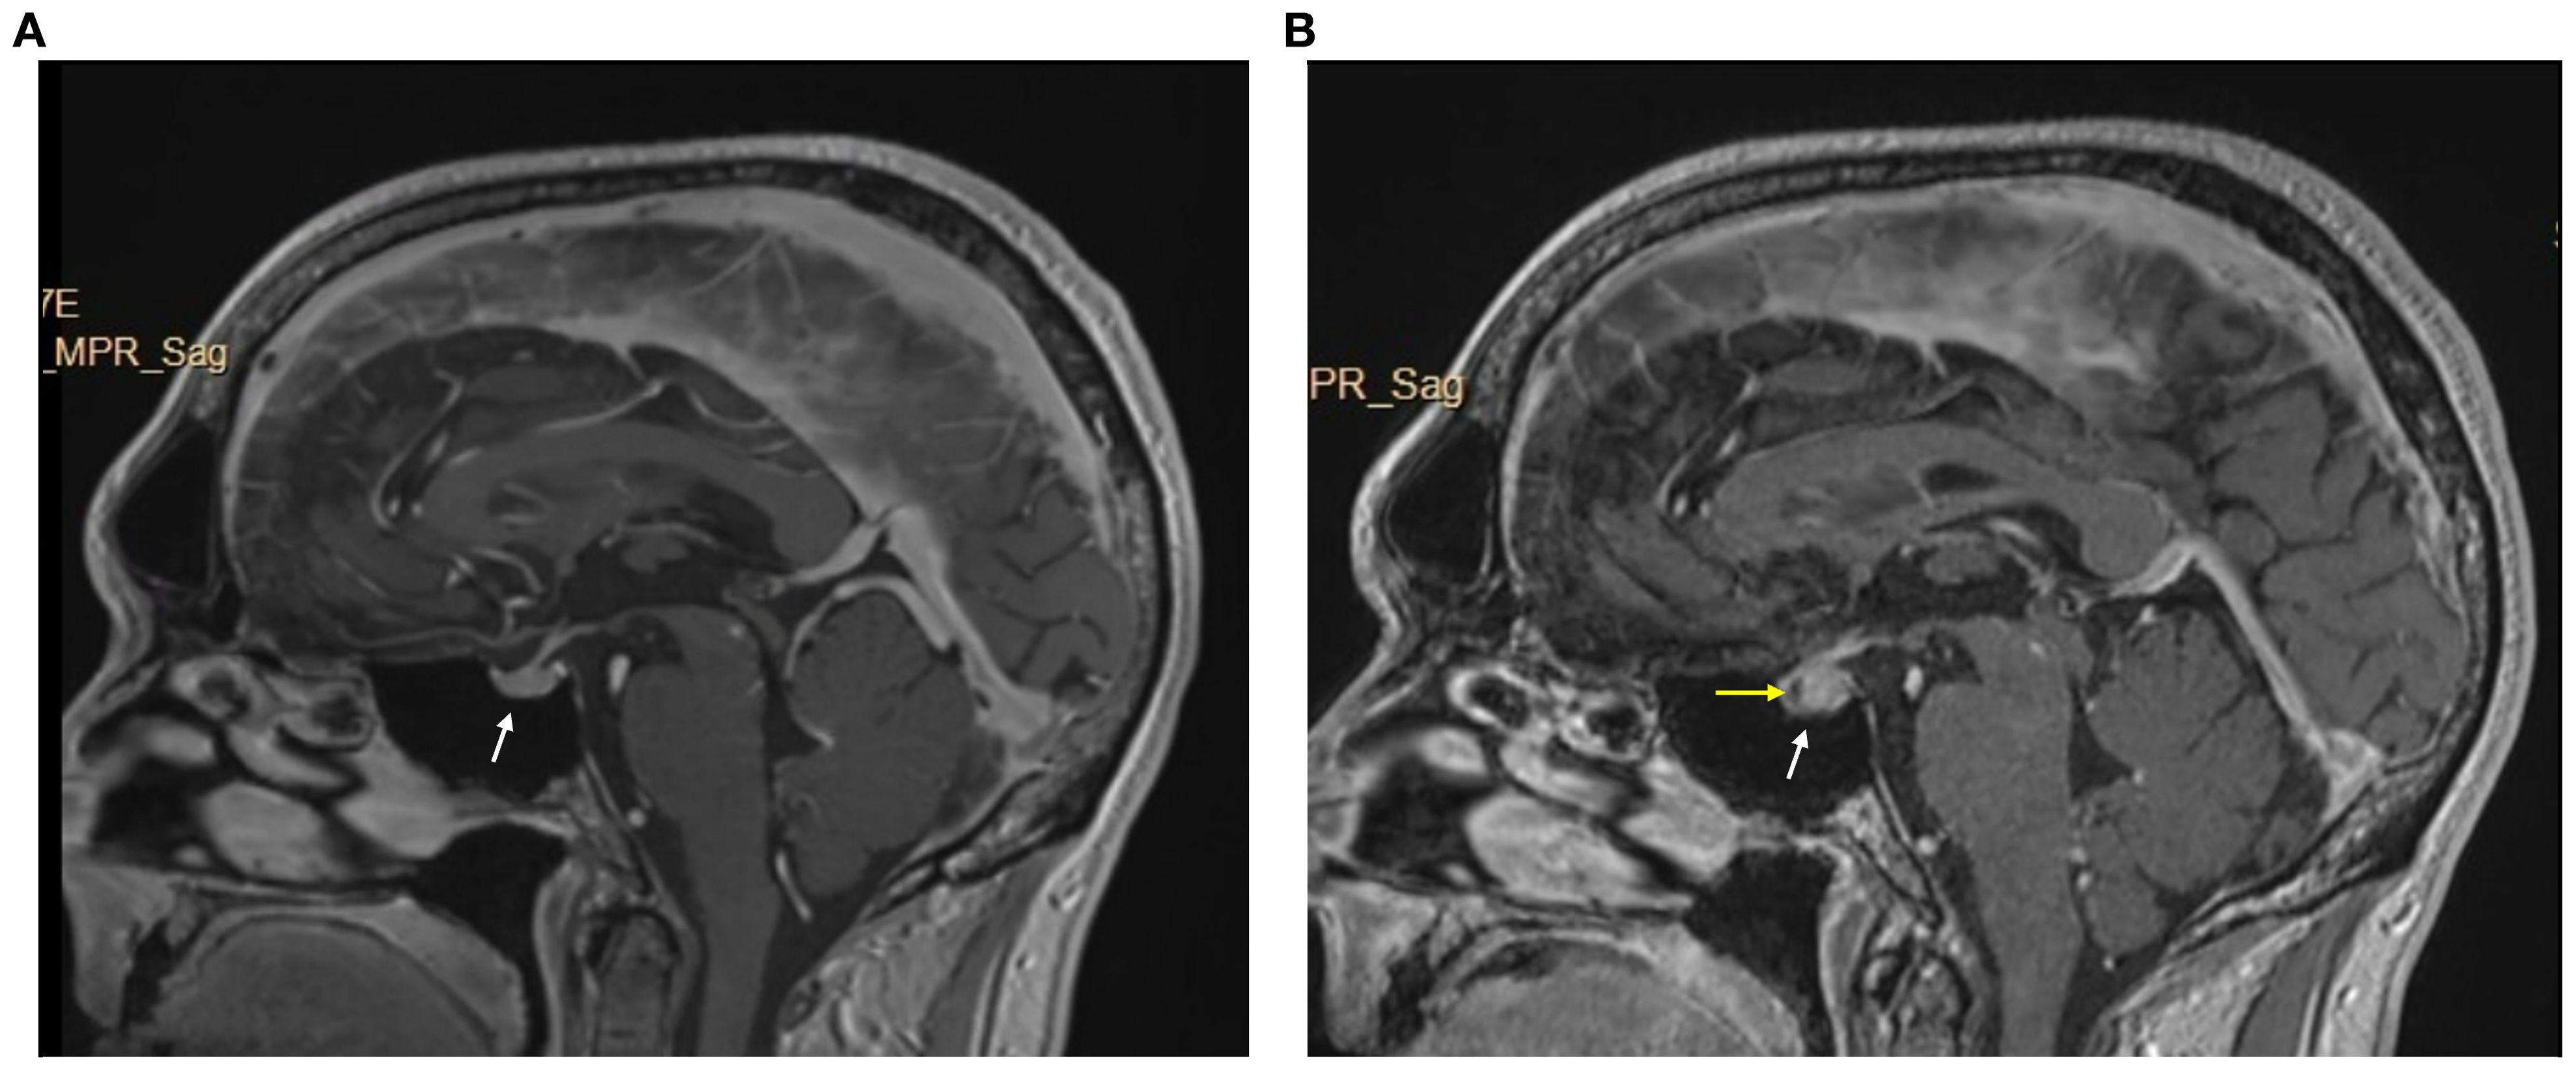

We report a case of a 60-year-old male with no significant medical history who presented with left axillary mass with pain for about 1 week. A positron emission tomography-CT (PET-CT) scan revealed hypermetabolic activity in the left axillary mass. A biopsy revealed metastatic stage IV melanoma of unknown origin (SOX10 positive, Melan-A positive, S100 protein positive) with a BRAF p.V600E mutation. A brain magnetic resonance imaging (MRI) scan was completed for staging, which revealed no brain metastases (Figure 3).

Figure 3. Brain MRI w/wo contrast pre- and post-immunotheraphy. (A) pre-immunotheraphy initiation; (B) post-immunotheraphy initiation.

He began pembrolizumab (400 mg) as neoadjuvant therapy and completed 5 cycles (24 weeks), with suboptimal response. The treatment was changed to ipilimumab (225 mg)/nivolumab (72.9 mg) as there was disease progression with metastasis to lymph nodes with extracapsular extension. After completing 3 cycles (7 weeks), he developed symptoms of diffuse muscle pain and fatigue requiring hospitalization. He was found to have abnormal blood chemistries including hyponatremia (sodium [Na], 118 mmol/L), hypocortisolism (cortisol, 1.01 mcg/dL), and hypothyroidism (thyroid-stimulating hormone [TSH], 0.274 uIU/mL, free thyroxine [T4], 0.66 ng/dL, free triiodothyronine [T3], 2.2 pg/mL). A brain MRI revealed an enlarged pituitary gland compared to his prior scan (from 9 months earlier), and with a new hypo-enhancing pituitary lesion (Figure 3). These findings were consistent with hypophysitis resulting in grade 3 adrenal insufficiency and grade 2 hypothyroidism (3). At this time, his myalgias were attributed to this endocrinopathy, and he was started on hydrocortisone (40 mg in morning/20 mg in evening) which was tapered to a maintenance dose (20 mg in morning/10 mg in evening) and levothyroxine (50 mcg).